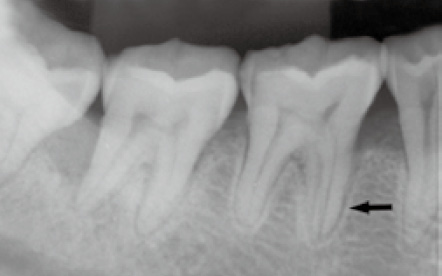

图 2

未经根管治疗的SVRF 女,46岁。X线片示46牙冠完好,根管空虚无充填物,近中根根管内径增宽,根尖孔扩大,牙周膜间隙增宽,牙根近中及根分叉区牙槽骨吸收。"